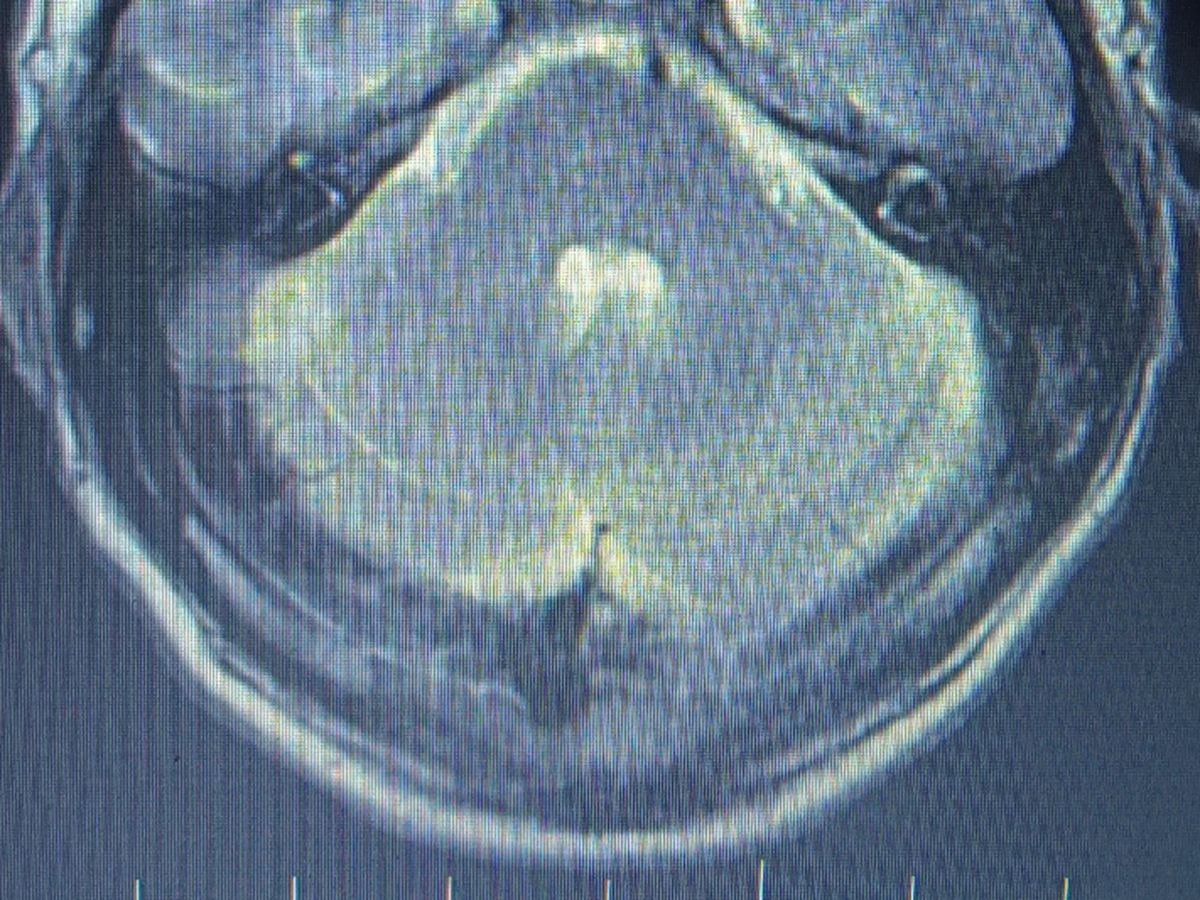

Hi, my name is Brett Waites. I'm 47, married with 3 children. Some of you know already but for those who don't, 18 years ago I was diagnosed with a brain tumor. 6 weeks of radiation therapy did a great job at shrinking it but unfortunately, it's growing again. I can't do radiation therapy this time because of my previous treatments. My only option now is surgery to remove it. Yeah, scary! This is going to be a long and expensive road and I will be out of work for a while. I will also have lots of medical bills during this time and I do not have health insurance. I'm not exactly sure how much this will all be but average brain surgey cost is around $100,000 not including MRI's, blood work, biopsy, medicine and other tests. Thank you in advance for anything and everything that you can do!